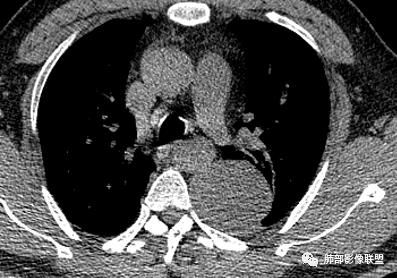

红日东升:左侧胸椎旁肿块,边缘清晰光整,冠状位见D字征,未见支气管进入,肺组织受压表现,定位肺外。轻度强化,密度稍不均匀,临近肋骨变细,未见肺动脉供血,考虑良性肿瘤,神经源性可能。右肺下叶病灶,轻度强化,血管显影,边缘平直、凹陷,考虑炎性病变。

张帅:患者中年男性,咳嗽 咳痰3月,痰为白色粘痰,左上肺病灶,边缘光滑,周围未见毛刺 分叶,肺组织受挤压,与胸膜关系密切,部分层面与胸膜脂肪间隙消失,有胸膜尾征,病灶定位于胸膜,病灶增强可见强化,边缘可见增强血管,内可见低密度区,考虑 孤立胸膜纤维瘤?神经鞘瘤?右肺下叶外基底段病灶,病灶与胸膜有牵拉,病灶边缘光滑,平直 u型征,未见明显毛刺,增强病灶内可见增强血管影,边缘低密度,考虑病灶内存在痰栓。右下肺病灶考虑良性炎症性病灶,ABPA?

王秀仙:左侧后纵膈占位,位于胸膜下,胸膜被顶起,有胸膜尾征,密度均匀,轻度强化,内可见斑点钙化。周围肺组织结构推移。右肺下叶可见片状影,沿支气管走行,边缘平直收缩,强化明显,胸膜有牵拉。二元论,考虑1左侧后纵膈神经鞘瘤。鉴别SFT.2右肺下叶炎性肉芽肿。

长沟流月去无声:中年男性,慢咳起病,左后纵隔可见一大占位,D字征,胸膜掀起,有胸膜尾征,附近肺组织受挤压,血管纹理纠集,瘤肺界面清晰,较均匀轻-中度强化,瘤肺表面可见线样不张之强化影,供血血管来源不易确定,冠状位似乎见一纵隔血管出入,综合考虑神经源性肿瘤:神经纤维瘤,神经鞘瘤?右下外斑片密度影,估计炎性,但本次手术应该未处理。

是这样,如果是胸膜来源的SFT,在脊柱和病灶之间应该会有脂肪层,但是这个脂肪层没有,所以不太考虑SFT,支持神经鞘瘤。而且供血看不清,似乎是这个。

南边:这个肯定是纵膈的血管,但是支气管动脉也可以从这里发出,但是没有连续的图,不知道跟病灶什么关系。

徐超:胸水在胸膜腔,图像太厚了首先肺外确定的,近脊柱如果是强化的壁层胸膜,与肿块间隙还有疑微积液,冠状位有一层胸膜外脂肪间隙存在清楚,都提示胸膜来源,主要是确定下内侧结构是否是壁层胸膜,如果是迎刃而解,如果胸膜外,无论哪一层壁层胸膜都是向肺的地方彭隆的。我也支持脏层可能大

平安是福:平扫31Hu,动脉期33–42Hu,静脉期,39–54Hu。

M-Imaging :冠状位,还是靠近纵隔来源的

南边:我觉得纵膈来源的